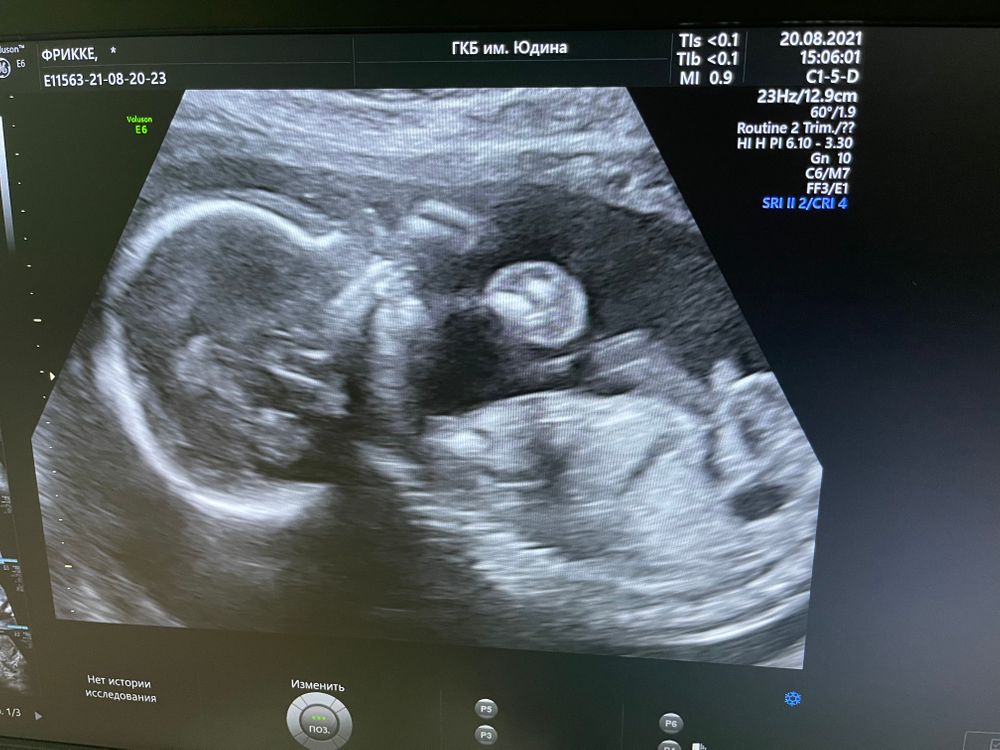

На память 19 нед и 4 дня , в платной на прошлой неделе ставили такой же срок 🙄 ну ладно ) 3 даты пдр 3, 7, 11 🙈

20.08.2021